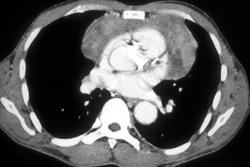

Pseudothrombosis in the Jugular Vein